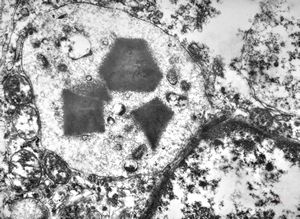

F,68y. | collagenous and elastin fibers from corium